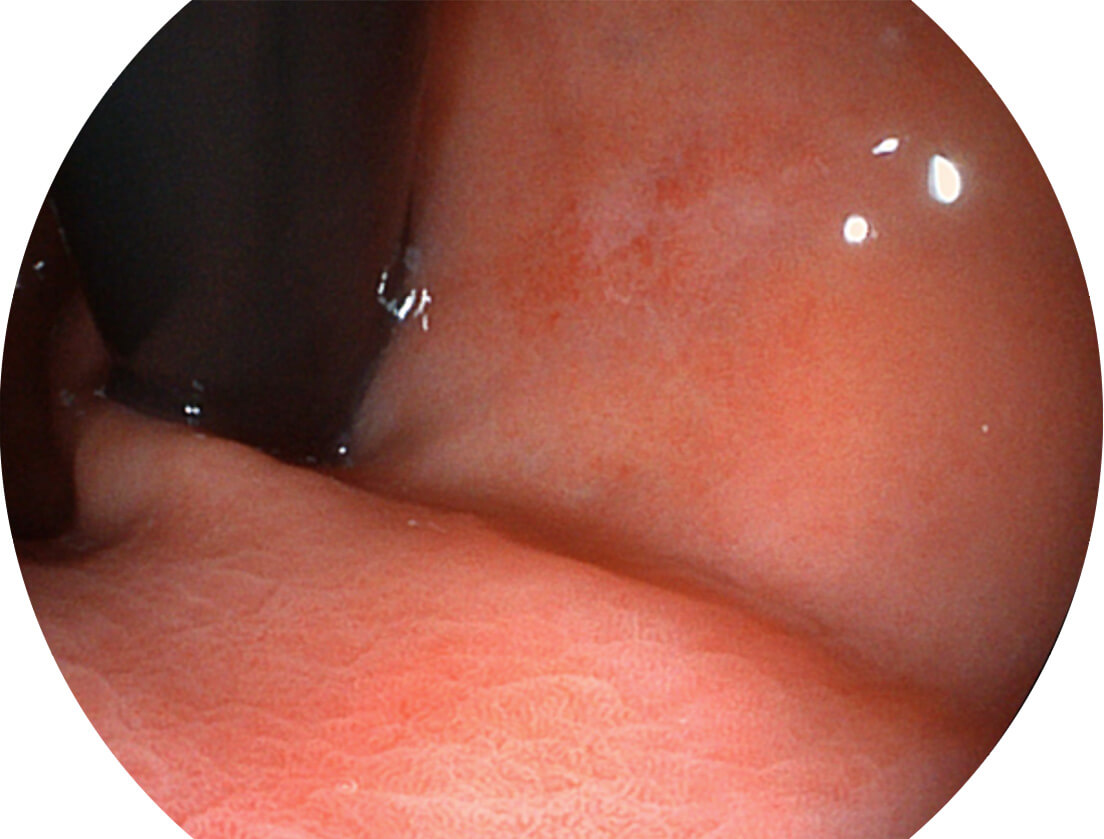

Versatile Intelligent Staining Technology, VIST

强调浅层黏膜结构的同时,保证照明亮度和提升浅层微血管与中层血管颜色对比度,病变边界更清晰。

VIST图像